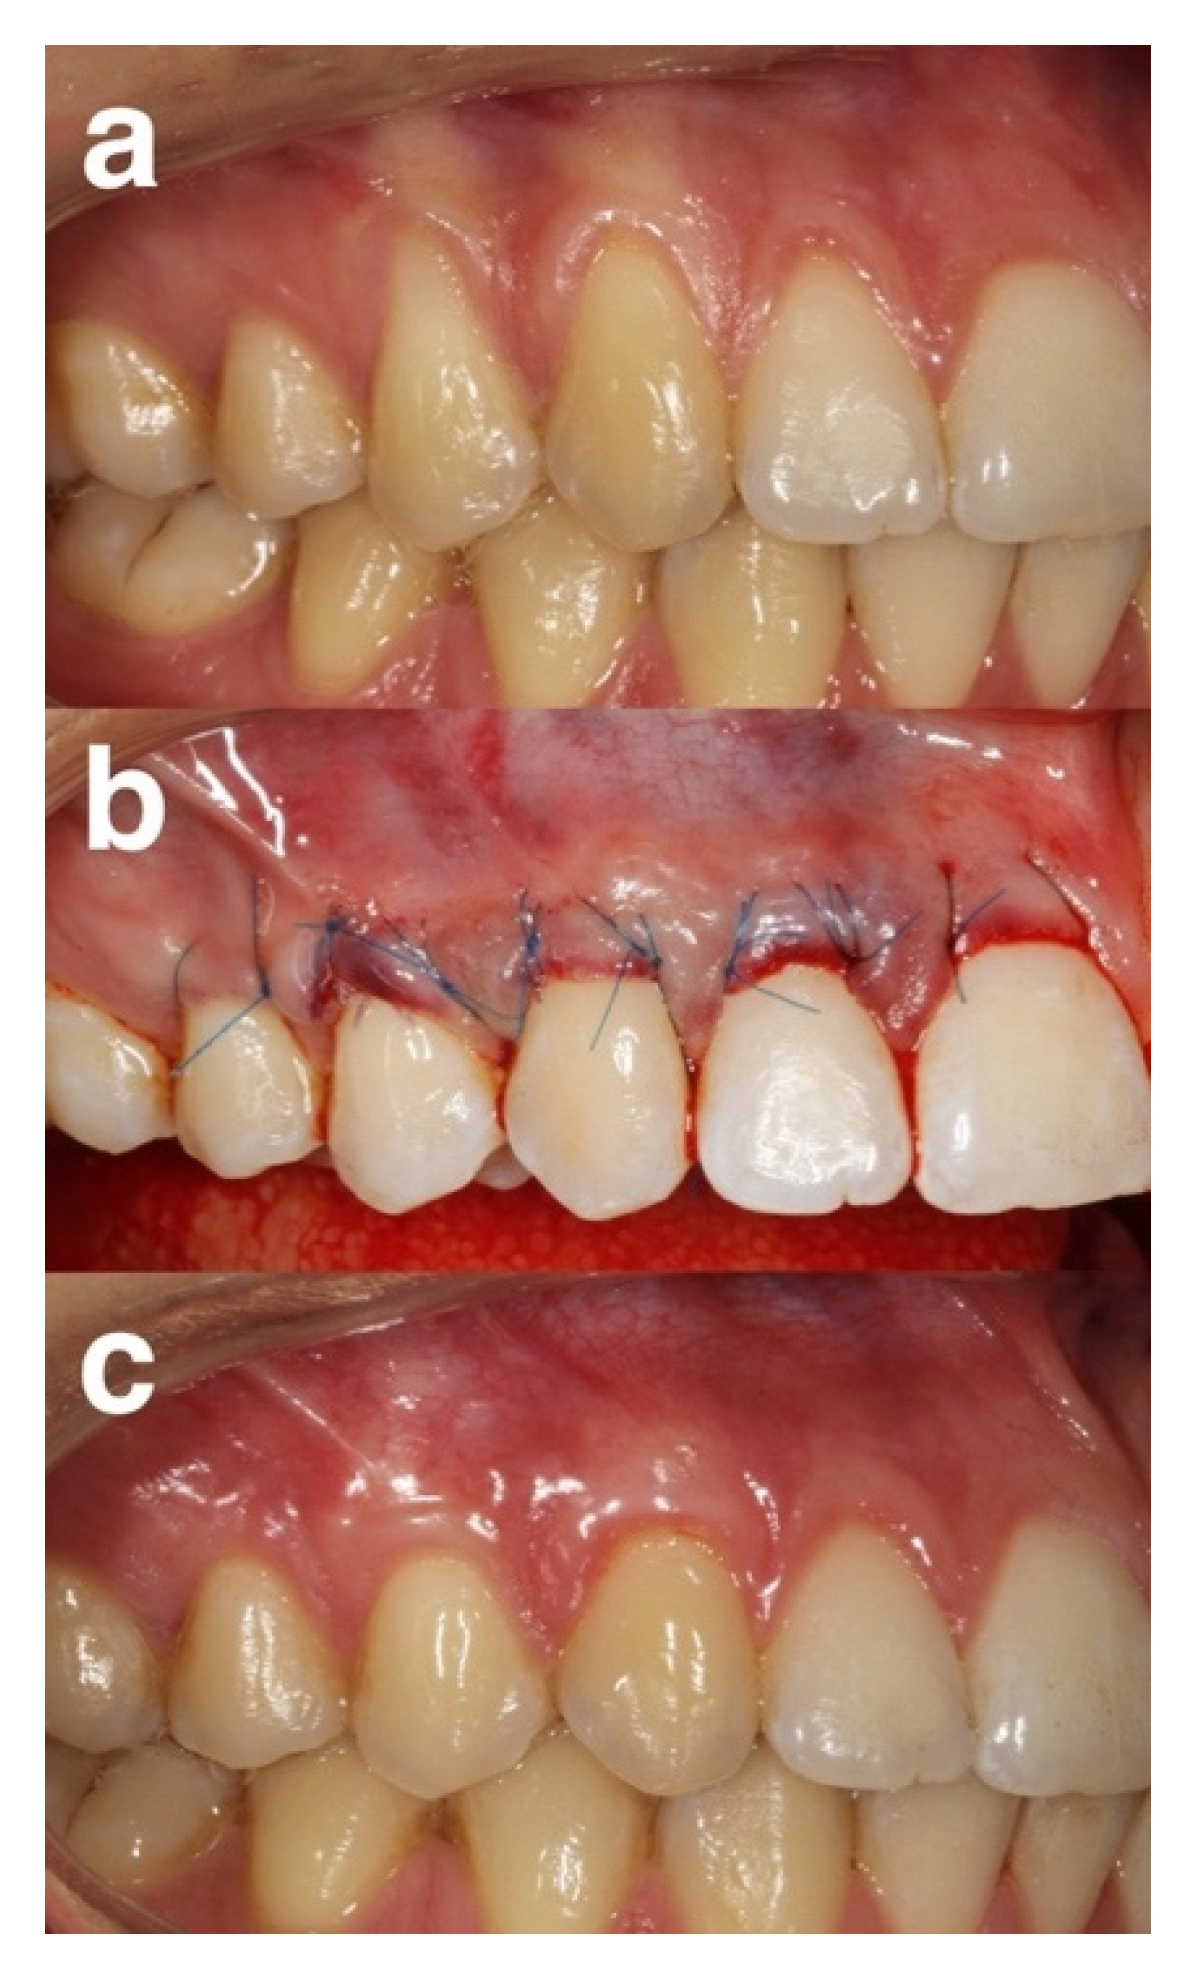

4.5. Surgical Phase